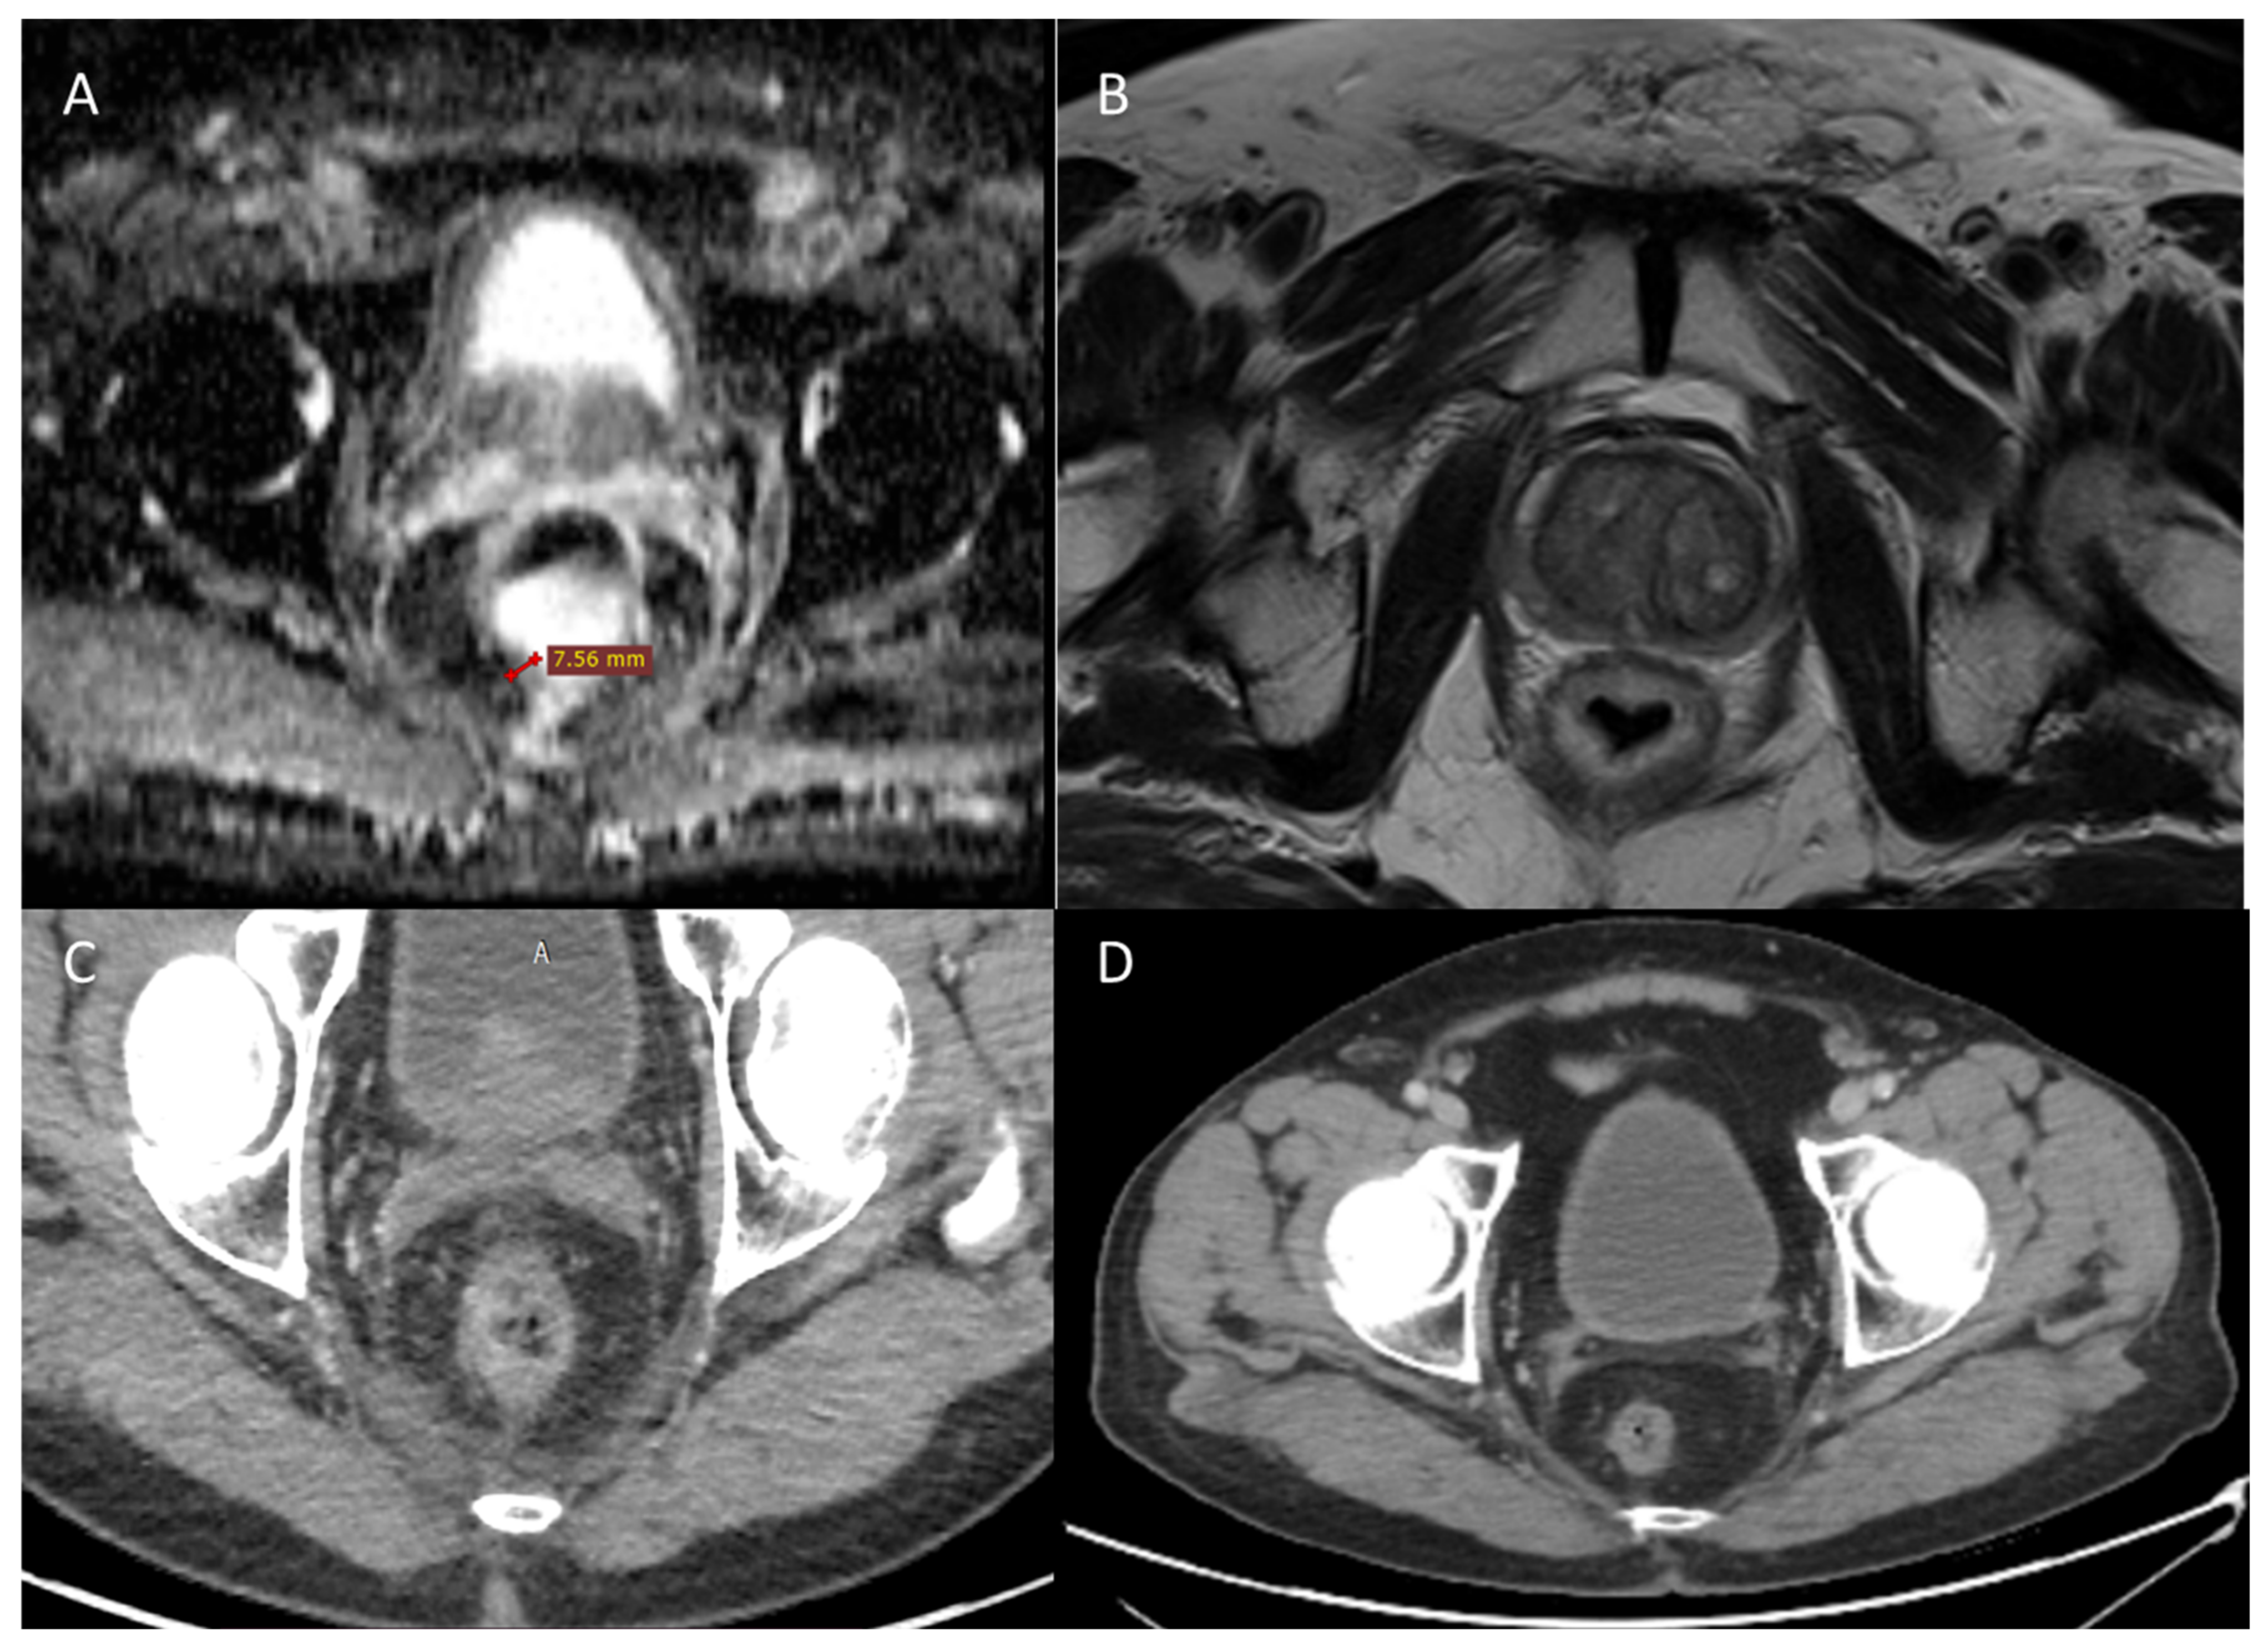

2.4. Third LARC Case Description

| 3 | Male 50 years old with recurrence after long course neoadjuvant therapy and total mesorectal excision (TME) treated with ECT | Variable and fixed geometry electrodes | MRI 6 months after ECT treatment showed no significant morphostructural changes in the lesion that was considered to be stable disease. Patient reported a reduction in pain on the VAS 7 to 4 scale and a reduction in bleeding. |